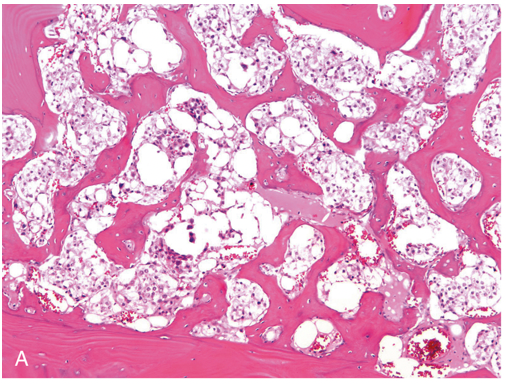

Q

mets that look like this

A

renal cell (clear cell)